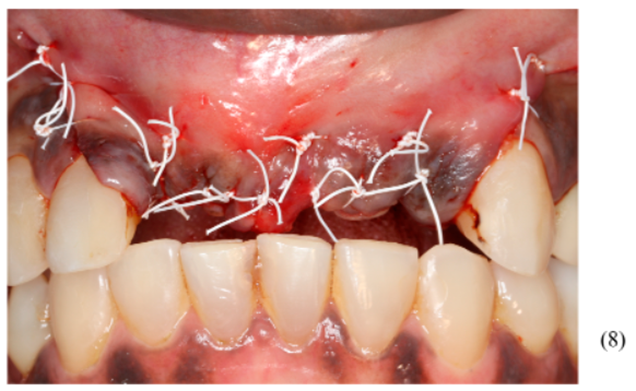

Figuras 3,4,5,6,7 e 8 – Sequência do primeiro ato cirúrgico, onde podemos observar (imagem 3) a incisão do tipo Newmann modificada para ampla visualização do campo operatório e as extrações dentárias. Podemos observar também a descorticalização do processo alveolar e a instalação dos parafusos tipo tenda Implacil De Bortoli de 10 mm, respeitando a distância de pelo menos 2 mm entre cabeças (imagem 4). Foram colocados dois gramas de biomaterial Bio-Oss Geistlich, preenchendo toda cavidade e alvéolos até a delimitação da cabeça dos parafusos (imagens 5 e 6). Antes do fechamento completo da ferida cirúrgica, colocamos membranas de PRF para auxílio na reparação tecidual e proteção do material de enxerto (imagem 7). Para fechamento da ferida cirúrgica, usamos fio do tipo Cytoplast, fornecido pela Implacil De Bortoli. É de extrema importância sua utilização, pois apresenta excelente elasticidade, acompanhando edema cirúrgico pós-operatório, o que diminui o risco de deiscência no pós-operatório.